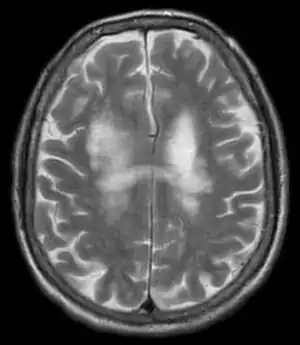

| یک تصویرMRI با وزندهی T2 که لکوانسفالوپاتی چندکانونی پیشرونده را در مغز نشان میدهد | |

هرگاه بیماری دچار علائم پیشرونده باشد و در مایع مغزی-نخاعی او نشانههایی از دیانای ویروس جیسی باشد و همچنین در تصاویر امآرآی مغز، ضایعات مرتبطِ مادهٔ سفید مشاهده شود، میتوان گفت فرد به لکوانسفالوپاتی چندکانونی پیشرونده مبتلا شدهاست. یک روش تشخیصی دقیق دیگر، بیوپسی مغز است[1] که در آن نشانههای رایج بافتشناسی تخریب میلین، آستروسیتهای غیرعادی و هستههای بزرگ اولیگودندروسیتها و یاختههای گلیال مشاهده میشود و با روشهایی، حضورِ ویروس جیسی اثبات میگردد.[11]

مشخصهٔ خاص لکوانسفالوپاتی چندکانونی پیشرونده در تصاویر سیتی اسکن، ضایعات کمتراکم چندکانونی بدون نیاز به ماده حاجب پرتونگاری و بدن اثرات فشاری است، اما MRI روشِ تشخیصی بسیار حساستری از سیتی اسکن است.[11] شایعترین نقاط درگیر در این بیماری لوب پیشانی، لوب آهیانهای-پسسری هستند، اما همهجای مغز همچون عقدههای قاعدهای، کپسول خارجی و ساختارهای موجود در گودی جمجمهای پسین همچون مخچه و ساقهٔ مغز هم میتوانند درگیر شوند.[11] جالب آنکه اگر لکوانسفالوپاتی چندکانونی پیشرونده ناشی از داروی ناتالیزومب باشد، ضایعت بیشتر به صورت تککانونی بوده و اغلب در لوب پیشانی قرار دارند.[11]